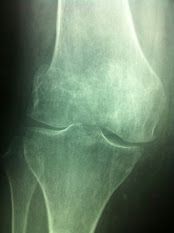

• Ortopedia del ginocchio

Salve sono un ragazzo di 27 anni e da ormai 17 anni soffro di problemi alle gambe in particolare alle ginocchia.

Dopo aver fatto un intervento in artroscopia bilaterale per asportazione cisti di baker e calcificazioni, alcuni anni anni più tardi a seguito di tac atgc con protocollo lionese mi sono sottoposto ad intervento di lateral release con mpfl (artherex) bilaterale.

Il dolore non diminuisce specialmente durante la giornata lavorativa mi vengono prescritti farmaci come palexia, targin, tauxib con esiti di condropatia rotulea bilaterale in esiti di plurimi interventi con limitazione funzionale ad entrambe le ginocchia.

Il dolore non diminuisce, si accentuano anche le parestesie bilaterali e effettuo infiltrazione bilaterale di lipogems, ma non apporta miglioramenti, anzi le ginocchia si infiammano.

Adesso gli esiti delle rm riportano

"presenti artefatti da pregresso intervento chirurgico sul profilo mediale della rotula con ispessimento, fibrosi e slaminamento del legamento alare mediale.

Infissione di vite al condilo femorale interno in sede di inserzione del legamento collaterale mediale che risulta un pò inspessite e con qualche aspetto di fibrosi.

Minimo edema della borsa prerotulea superficiale medie con modesto versamento nella guaina del popiliteo.

Un pò inspessito il tendine rotuleo in corrispondenza dell'inserzione alla apofisi tibiale anteriore che appare lievemente dismorfica in verosimili esiti di malattia di Osgood-Schlatter e con minime note degenerative nel restante ambito.

Regolari i restanti tendini e legamenti.

Note di condropatia femoro-pattellare di secondo grado senza segni di edema spongioso dell'osso subcondrale.

"